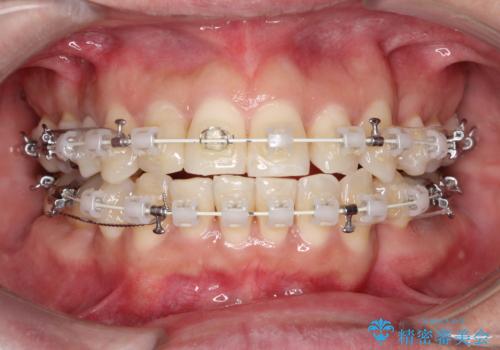

- 治療計画

- 治療計画: 重度の叢生を改善するため、上下左右の小臼歯抜歯を伴う審美ワイヤー矯正を計画しました。抜歯により得られたスペースを利用して歯を整列させ、適切な噛み合わせを目指します。途中、患者様が1年間の海外出張となったため、一時的にワイヤーを外し、保定装置で現状維持を図りました。帰国後に再度審美ワイヤー矯正を再開し、仕上げ調整を行い治療完了を目指します。

重度の叢生により、抜歯を伴う矯正が必要と判断しました。目立ちにくい透明な審美ブラケットを用いたワイヤー矯正を実施しましたが、治療途中での海外出張が決定したため、一度矯正装置を取り外し、保定装置で現状維持を行いました。帰国後に改めて装置を装着し矯正を再開。患者様のライフスタイルに柔軟に対応しながら、最終的には理想的な歯並びと美しい口元を実現しました。